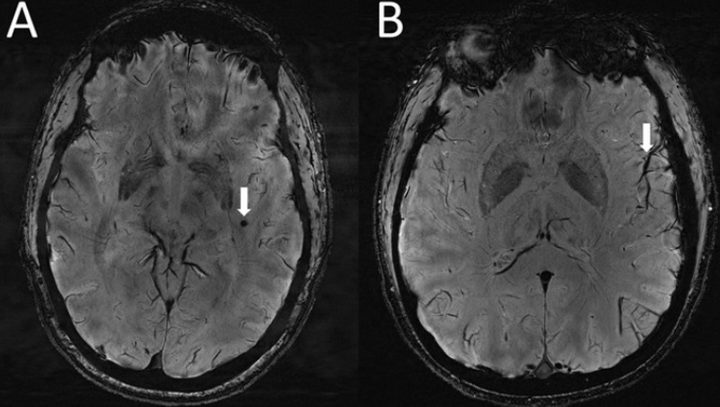

En ambos grupos de migraña, el equipo encontró un mayor número de espacios perivasculares agrandados, que son bolsas llenas de líquido ubicadas cerca de los vasos sanguíneos en ciertas partes del cuerpo, incluido el cerebro. Estos espacios eran más prominentes en el centro semioval, el área central del cerebro de la materia blanca. También encontraron que la presencia de estos espacios estaba relacionada con lesiones de sustancia blanca, aunque no hubo una diferencia significativa en la gravedad de las lesiones encontradas en personas con o sin migrañas. Los hallazgos se presentarán el miércoles en la reunión anual de la Sociedad Radiológica de América del Norte (RSNA).